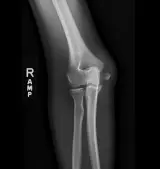

MSK Radiographs

Peds Radiographs

Review cases with classic "textbook" pathology. Once you've mastered the basics, move on to practice cases with more challenging or subtle findings.

Oftentimes the key to nailing a difficult radiology case is having seen a similar case before. Practice with over 1,500 carefully selected cases covering a comprehensive list of diagnoses.

Master classic and atypical appearances of pathologies more efficiently than haphazardly reviewing cases at work. Cases include sample reports, focused discussions, annotated images, and reputable references.